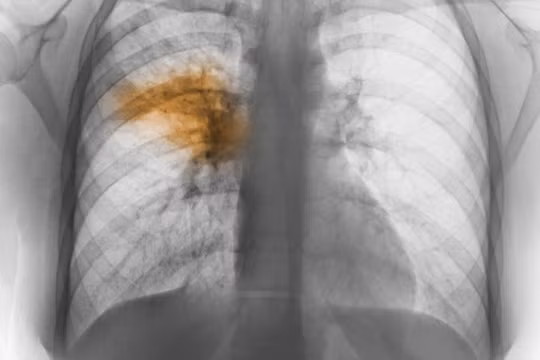

Mới đây, Bệnh viện Bạch Mai tiếp nhận một bệnh nhân nữ 28 tuổi (Thái Bình) đang mang thai ở tuần thứ 17 và xuất hiện những cơn ho. Nghĩ là mắc bệnh hô hấp thông thường, bệnh nhân tự ý điều trị tại nhà nhưng tình trạng bệnh càng nặng hơn, tình trạng khó thở bệnh nhân mới nhập viện điều trị. Lúc này bệnh nhân đã trong tình trạng viêm phổi .

Cũng trong thời gian này bệnh viện tiếp nhận một bệnh nhân nam 55 tuổi có tiền sử sử dụng rượu bia lâu năm. Bệnh nhân nhập viện trong tình trạng viêm phổi có biến chứng suy hô hấp phải thở oxy, nguy cơ tử vong cao.

Viêm phổi là tình trạng nhiễm trùng tại nhu mô phổi và phế quản của người bệnh. Có nhiều nguyên nhân gây ra viêm phổi như: virus, vi khuẩn, ký sinh trùng, nấm, hóa chất… Đối với trường hợp nhiễm viêm phổi do các vi khuẩn đặc biệt hoặc virus sẽ gây ra tình trạng diễn biến bệnh nặng thậm chí suy đa phủ tạng, suy hô hấp gây tử vong.